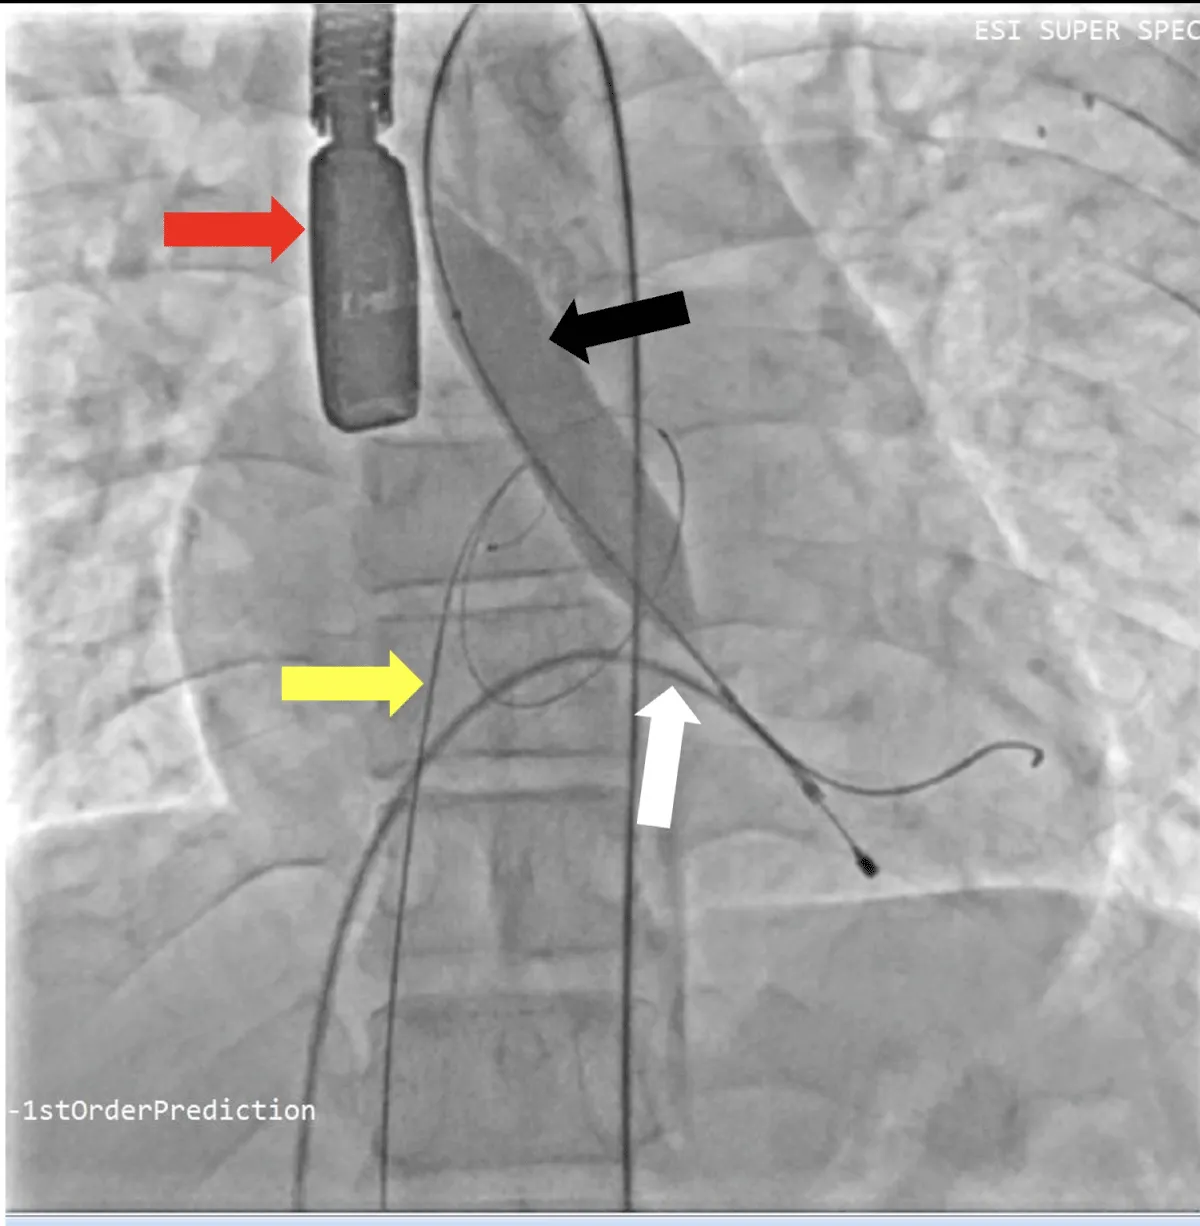

After obtaining consent, access was obtained through the right femoral vein and artery. Under 4D Transesophageal Echocardiography (4D TEE) guidance, the first transseptal puncture was performed with a broken Brough needle, and the LA wire was inserted through femoral venous access (Figure 1). Right femoral artery access was used for retrograde crossing of the aortic valve (AV) (Figure 2), and a Teflon wire was placed in the left ventricle. The aortic valve (AV) was dilated with a 14 mm ATLAS GOLD (BARD) balloon (Figure 3, Video 1).

Figure 1: A,B: 4Dimensional multiplanar transoesophageal echocardiography. A. 4D image with Left atrial wire, B. Severe mitral stenosis with mitral area of 0.5 cm2, 1C &1D. Showing multiplane of mitral valve.

Figure 3: Fluoroscopic image of aortic valve. Balloon dilatation of aortic valve under fluoroscopy and transoesophageal echocardiography (Red arrow), yellow arrow – Left atrial wire, white arrow- Right ventricular pacing lead, black arrow- Balloon across the aortic valve.